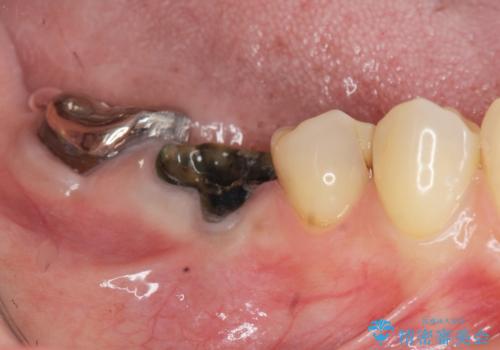

銀歯の下に大きな虫歯の再発

「 セラミック治療 」奥歯を白くしたい